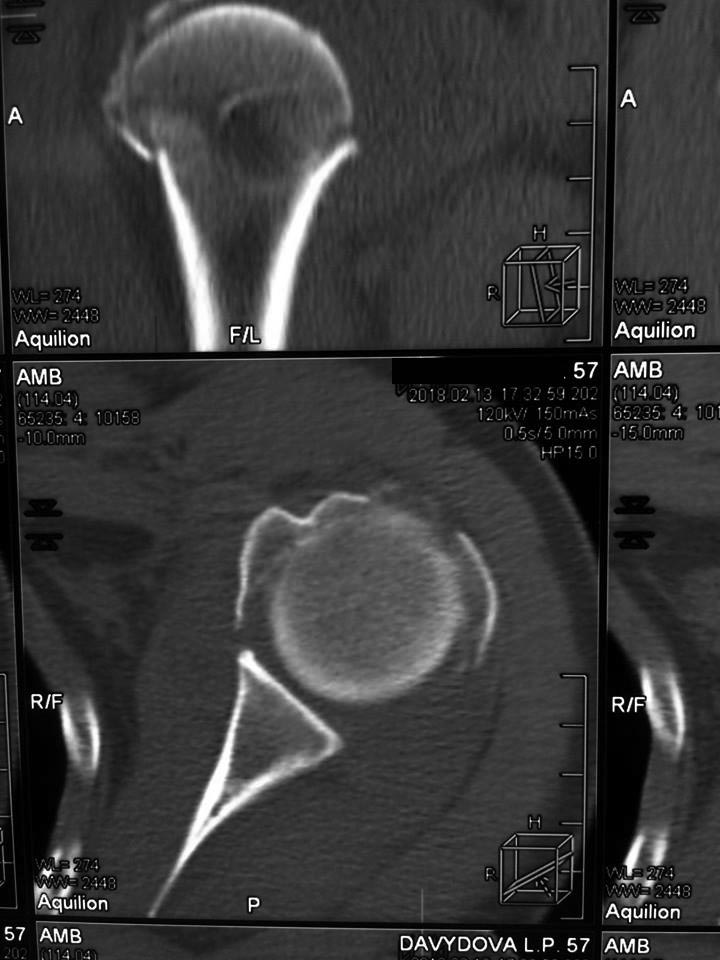

На снимках плечо вывихнуто. По ркт- открытая репозиция и пластина с угловой стабильностью LCP . Все просто.

Делать синтез. Пластиной. Быть готовым к костной пластике после оппозиции головки. Главное вернуть на место бугорки с манжетой. Можно и протез но не реверс а анатомический.

Cмотря какие требования пациента. риски аваскулярного некроза высокие в любом случае. протез поставить всегда успеет, в случае некроза функция сравнима с эндопротезом

В возрасте до 60 лет - ORIF. Пластика не нужна. Самое важное прошить и фиксировать сухожилия манжеты к имплантату. Я бы предпочел Multiloc.